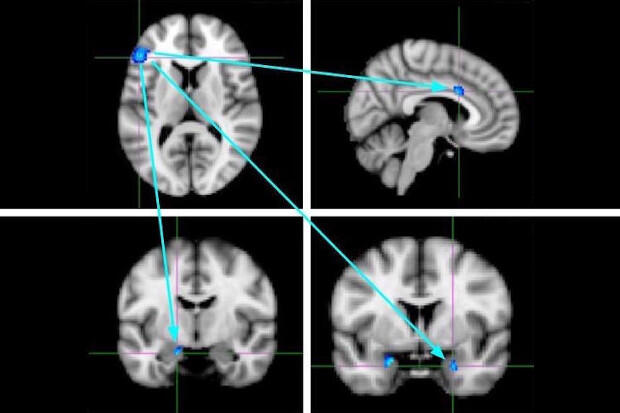

A team of researchers observed functional brain imaging in an MRI scanner while the participants were first socially accepted and then rejected. (Courtesy photo)

The link between mindfulness and reduced social distress also was seen in the brain imaging, as researchers found there was less activation in the left ventrolateral prefrontal cortex, which is known to assist in the “top-down” inhibitory regulation of both physical and social forms of pain.

The researchers also examined the communication between the ventrolateral prefrontal cortex and other brain areas during social rejection. They found that more mindful individuals showed less functional connectivity between the ventrolateral prefrontal cortex and two brain regions that help generate the experience of social distress, the amygdala and the dorsal anterior cingulate cortex.